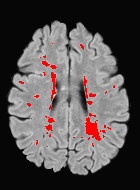

Patch size is another important parameter of the network. In computer vision applications such as object detection, usually a whole 2D image is used as a feature. However, full 3D medical images can not typically be used because of memory limitations. Fig. 4 shows examples of lesion memberships obtained with different sized 2D patches. As the patch sizes increases, the false positives that are mostly observed in the cortex tend to decrease. Fig. 5 shows a plot of Dice and LFPR with various patch sizes, ordered from left to right according to their increasing size. Note that smaller patches ( to ) produced significantly lower Dice and higher LFPR compared to other patches (), as seen from the memberships in Fig. 4. Also some of the highest Dice and lowest LFPR were observed for patches with large in-plane size, i.e., , , and . It was observed in Fig. 5 that there is no significant difference between Dice coefficients for , , or , but LFPR of both and are significantly lower than that of (). We chose as the optimal patch size. Other choices of smaller and patches (not shown) yielded worse results. Note that although training was performed with different patch sizes, the memberships were generated slice by slice, as the trained model consisted only of convolutions and did not need any information about patch sizes.

In our experiments, we used large 2D patches similar to Ghafoorian et al. (2017b), in comparison to isotropic 3D patches as used before, e.g., in Valverde et al. (2017), in Wachinger et al. (2017), and in Kamnitsas et al. (2017). The rationale behind using large anisotropic patches is twofold. First, experiments with full 3D isotropic or patches showed little or no improvement in Dice and led to increased false positives, with memberships similar to the one with patches, as shown in Fig. 4. Larger isotropic patches, e.g. or , showed inferior segmentation, and in some cases, optimization did not converge. The reason is that the FLAIR images in the test datasets had inherently low resolution in the inferior-superior direction, mm and mm compared to in-plane resolution of mm. Therefore 2D axial patches capture the high resolution in-plane information that represents the original thick axial slices. Second, the lesions are usually focal and small in size, unlike other brain structures. Therefore a very large isotropic patch around a small lesion can include superfluous information about the lesion, which can increase the amount of false positives. Note that with in more recent studies employing high resolution 3D FLAIR sequences, it is trivial to extend the algorithm to accommodate for 3D patches.